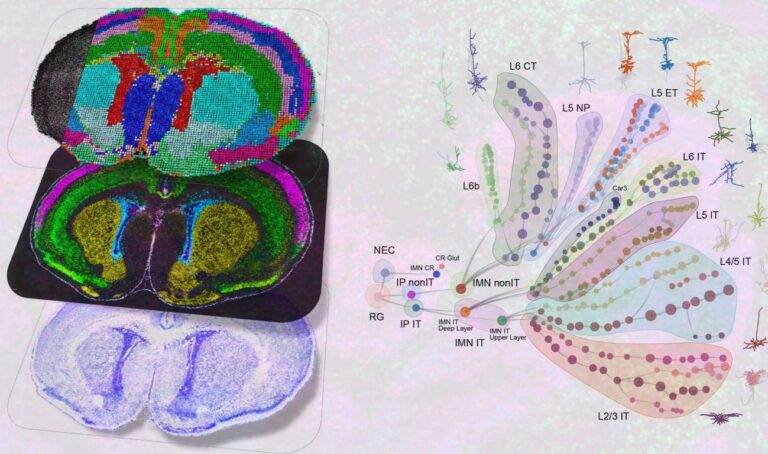

El cerebro humano contiene miles de tipos de células que se forman a partir de procesos de...